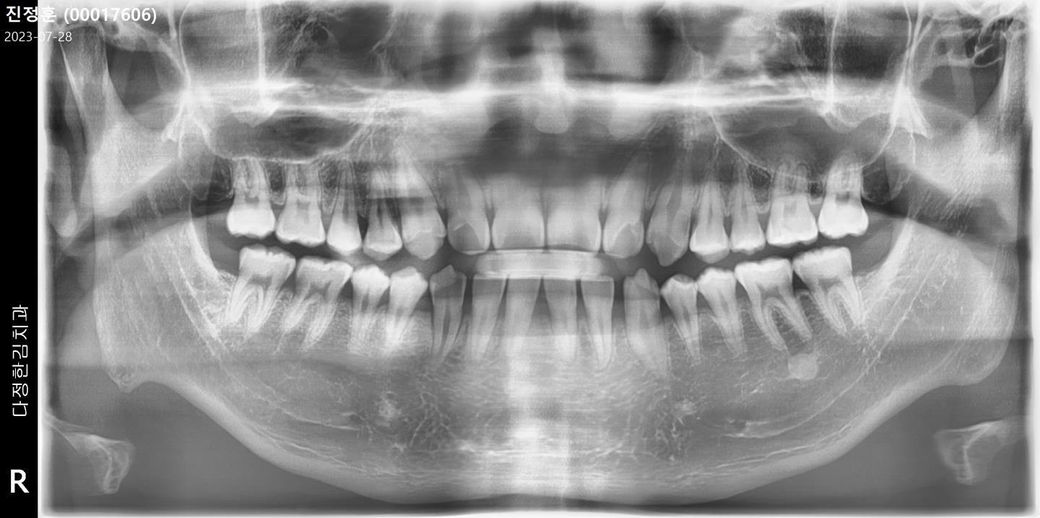

왼쪽 상단 2번쨰 어금니입니다

첨부사진은 지난주 엑스레이 사진입니다

• 1번 째 사진

엑스레이 상으로 보면 잇몸도 안좋으신거 같고 치아에 충치가 생긴것처럼 보이기도 합니다. 시린증상이 심하시다면 치료를 받으셔야될것같습니다.

현재 엑스레이상으로는 이상이 확인이 되지는 않으며, 치아에 통증이 심한 경우레진안쪽으로 충치가 발생하였을 가능성이 있기에 다시 치과를 방문하여 진료를 받길 권합니다.